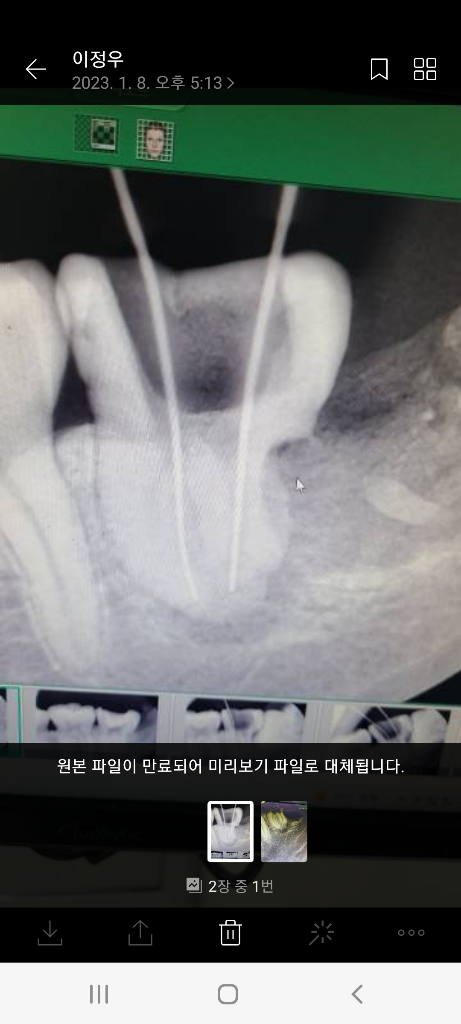

2. 23.1.8 사진 (임플란트 권유 시점)

• 2번 째 사진